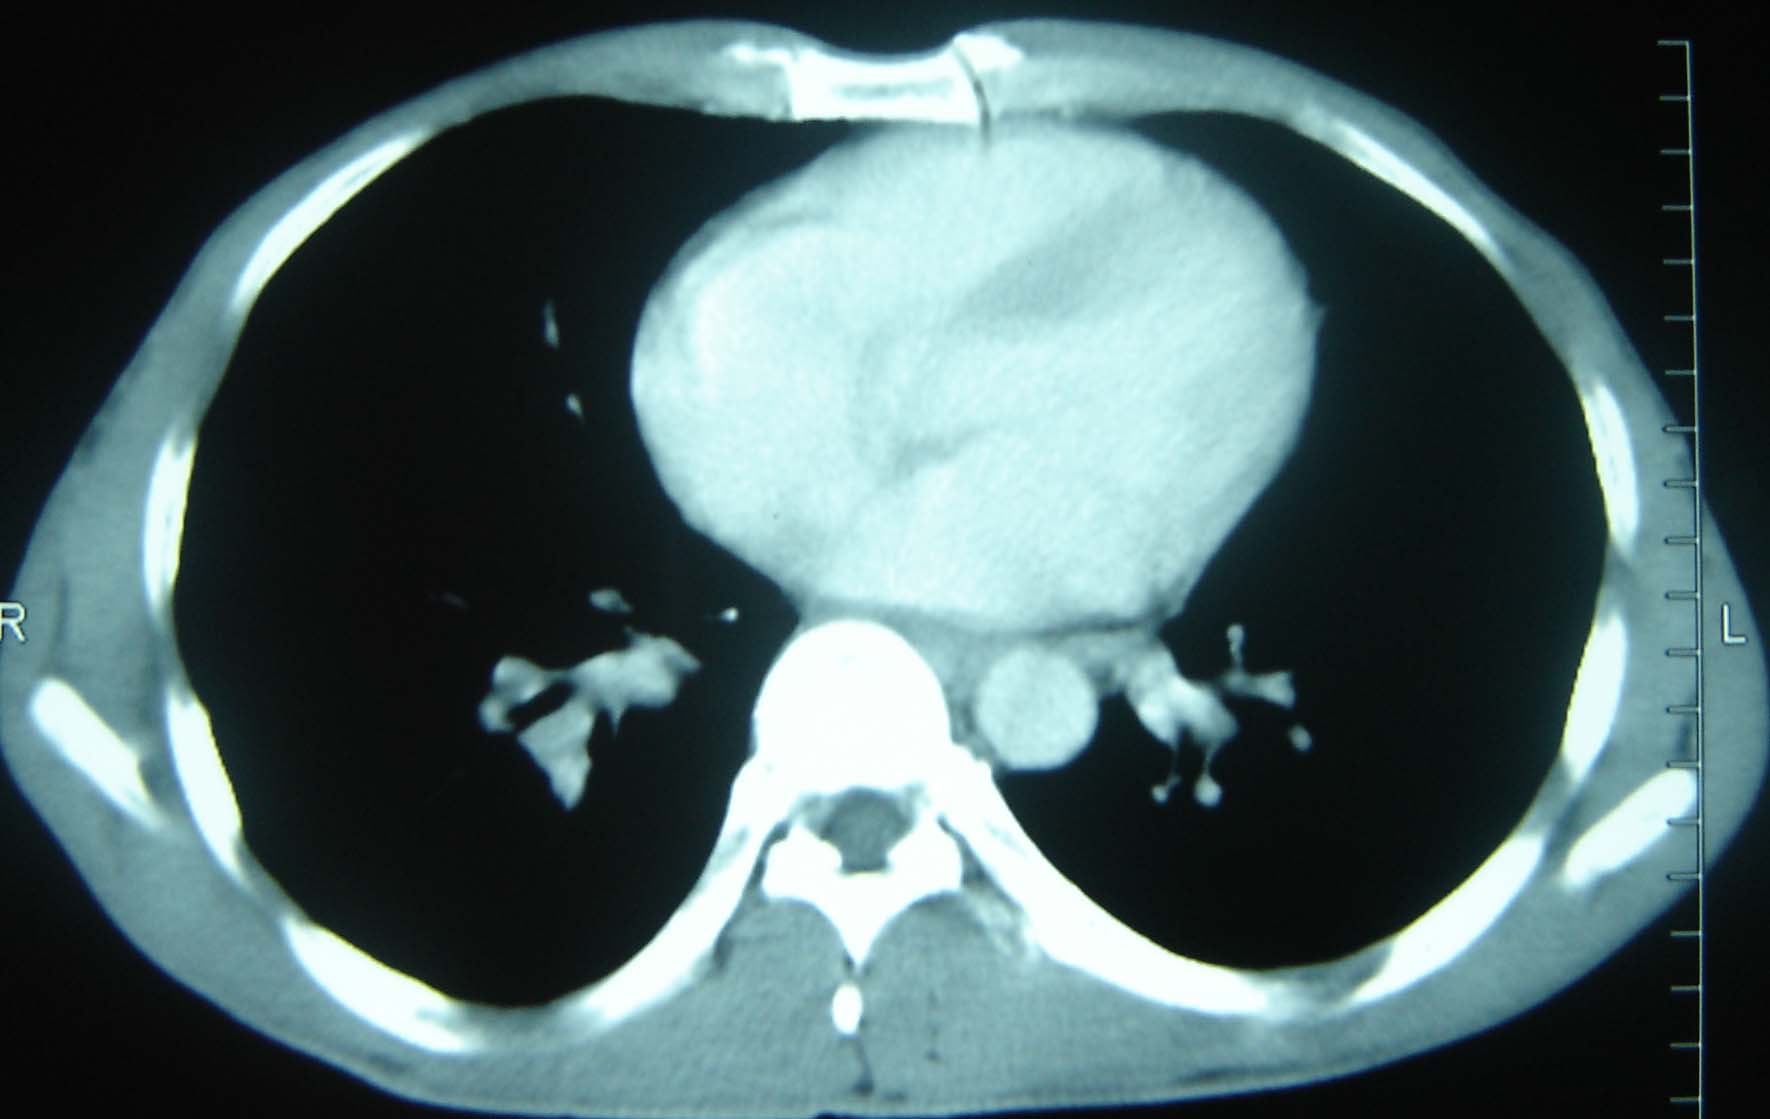

标题: CT25321:两肺多发结节 请会诊 [打印本页]

男 、43岁,咳嗽胸痛,装修工,平时接触粉尘较多,有吸烟史10多年,纤维支气管镜检查未发现异常,胃镜、腹部b超检查亦未发现异常,颈部淋巴结活检未发现肿瘤细胞。